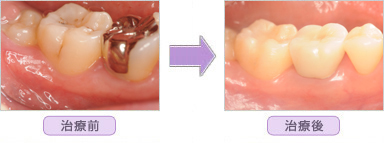

ハイブリットセラミックインレーの治療紹介

■ 右下臼歯部1本セラミック T.S様 27歳 女性

■ 右下臼歯部2本セラミック H.O様 35歳 女性

■ 右下臼歯部3本セラミック S.M様 36歳 女性

■ 左上臼歯部2本セラミック A.K様 36歳 女性